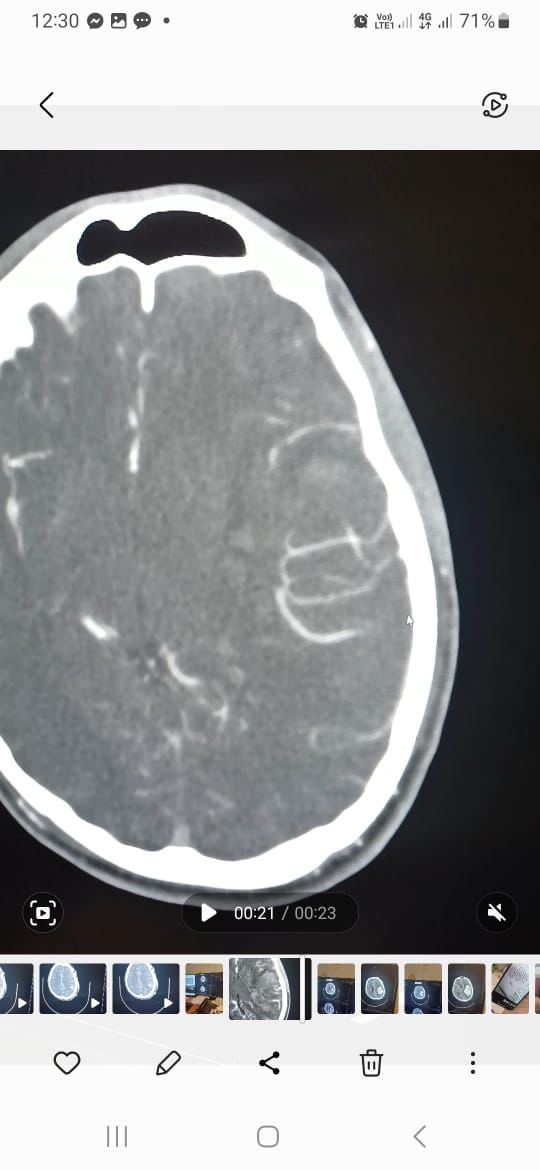

تمكن بفضل من الله فريق طبي من  قسم جراحة المخ والاعصاب  بمستشفى الملك خالد التابع للتجمع الصحي بتبوك من انقاذ حياة شاب بالعشرين من عمره وصل الى قسم الطوارئ وهو في حالة فقدان للوعي وبعد عمل الفحوصات اللازمة وتصوير الاوعية الدموية الدماغية تبين وجود نزيف دماغي حاد في الجهة اليسرى كذلك وجود تشوه خلقي دموي وعائي كبيرا جدا.

واكد الفريق الطبي بان حالة المريض تحسنت تدريجيا ولم تكن هناك أي مضاعفات اثناء وبعد العملية وبدا بحركة الأطراف إضافة الى فتح العينين ولله الحمد.